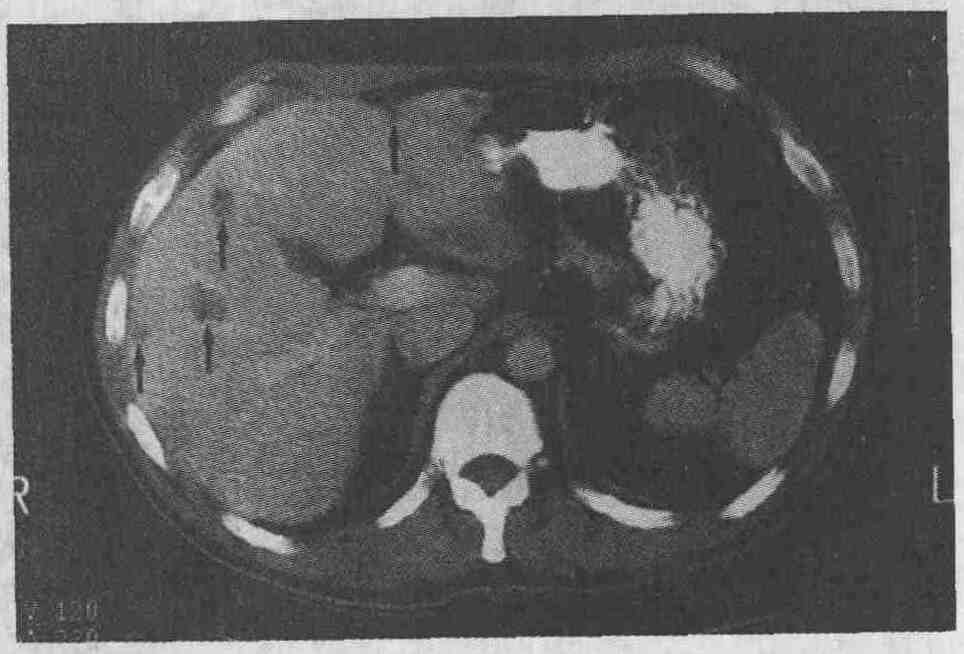

На компьютерных томограммах в большинстве случаев метастатические поражения печени выглядят как участки, имеющие меньшую плотность, чем окружающая паренхима (см. рисунок); однако метастазы рака островковых клеток поджелудочной железы, почечно-клеточной карциномы, карциноидных опухолей, рака щитовидной железы могут выглядеть более плотными.

Метастазы печени (стрелки) у пациента с раком ободочной кишки имеют меньшую плотность по сравнению с плотностью неизмененной паренхимы печени